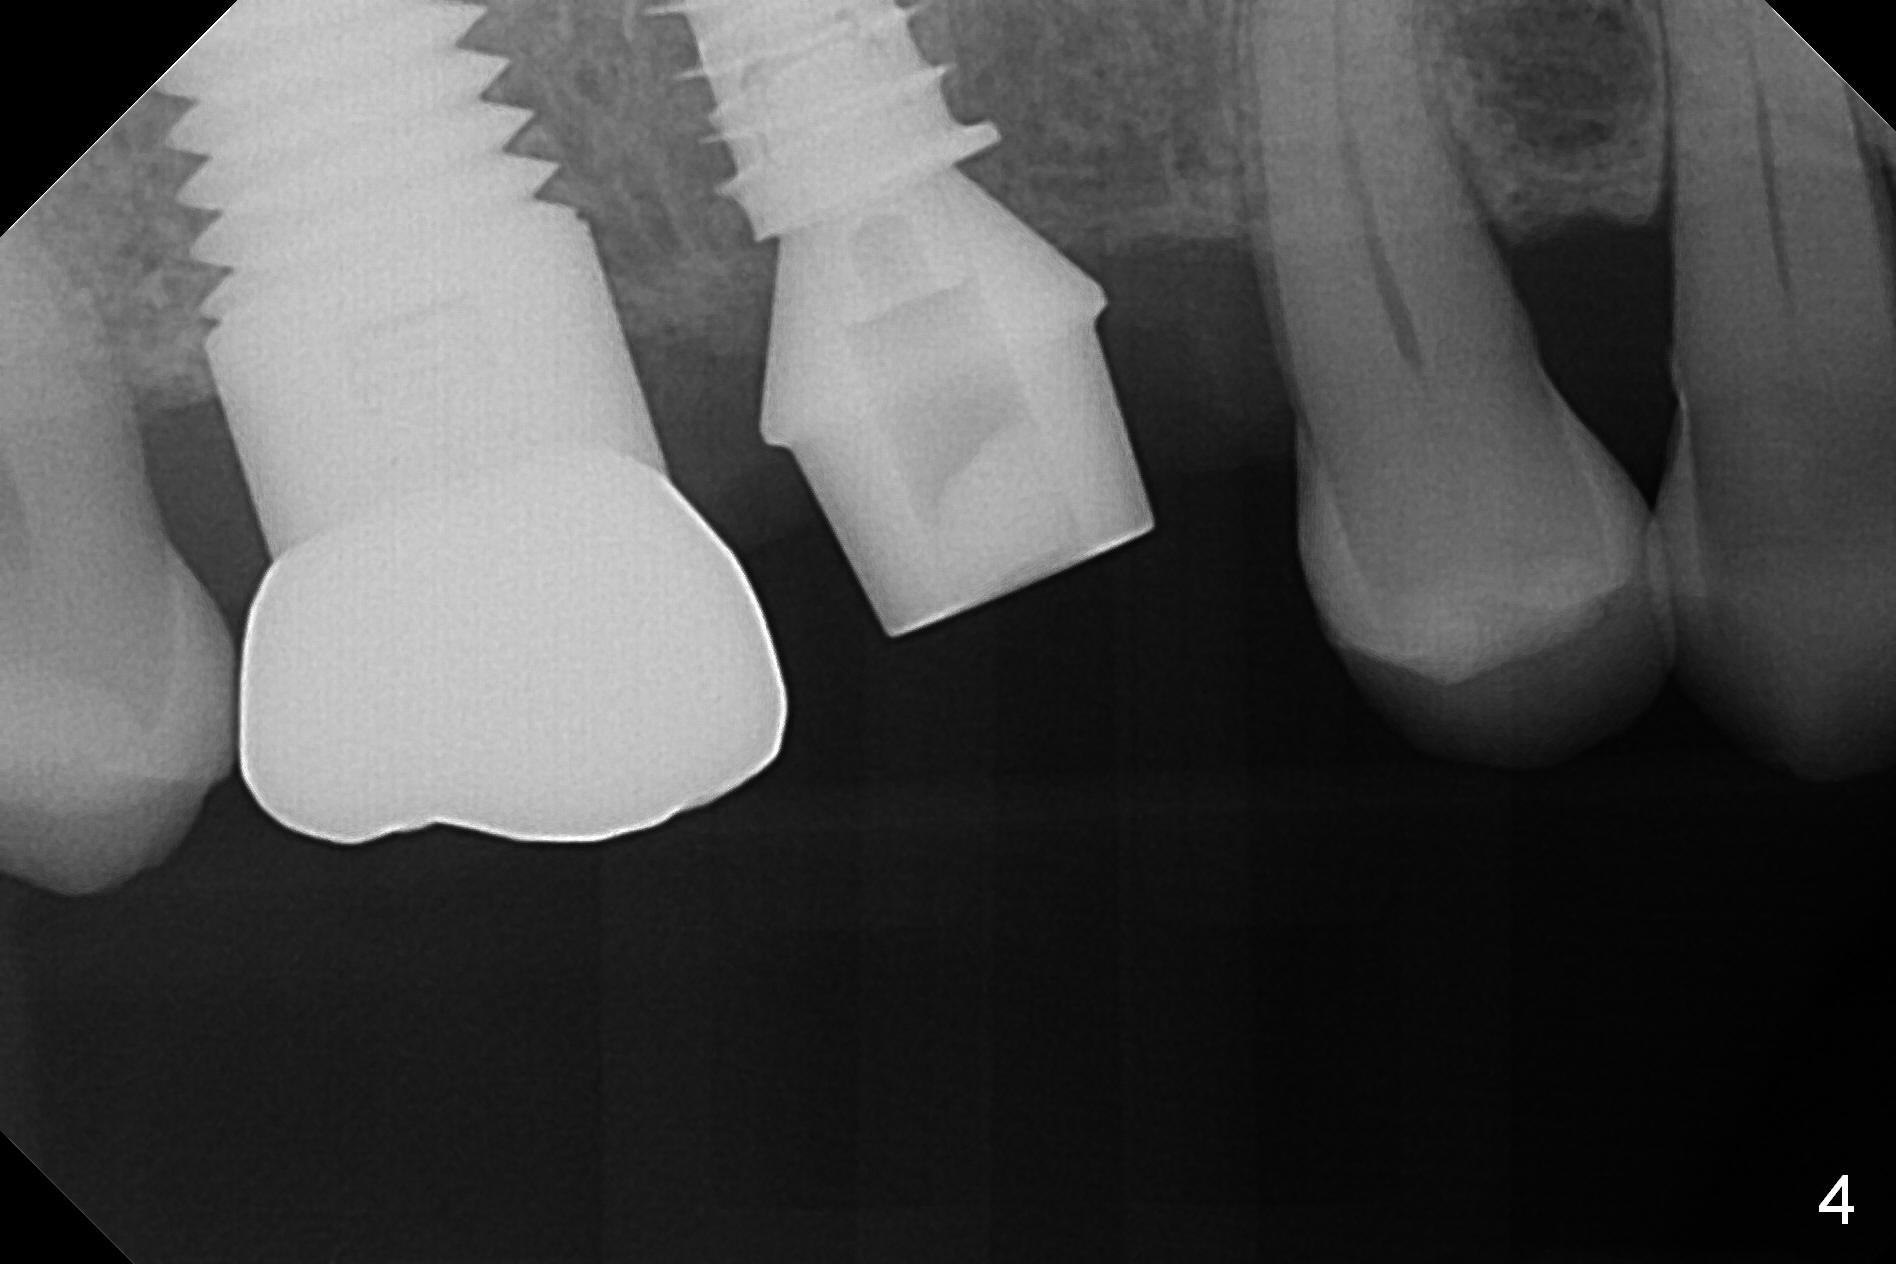

Heavy bruxism is characterized by the crack at #3 (symptomatic, requiring emergency extraction) and loss of the palatal cusp at #5 (Fig.1). Osteotomy is initiated in the septal slope (Fig.2 S) with a 1.6 mm pilot drill for 9 mm (with sudden empty feeling), followed by Marking bur. After 4.3 mm Magic Drill is used for ~ 9 mm, the sinus membrane is found to perforate. A dummy implant (5x9 mm, 2 mm shorter than design) is placed short of the sinus floor (Fig.3 ^). Prior to placement of 5.5x9 mm IBS implant (~ 35 Ncm, Fig.4,5), a piece of Osteogen plug is inserted into the osteotomy for repair of the perforation. The final implant is also shy of the sinus floor (Fig.5 ^). The Osteogen plug is apparently placed underneath the sinus floor so that it should be able to repair hard and soft tissue defects. The remaining sockets are mainly filled with Osteogen plug, while the implant plateau is covered by autogenous bone and Osteogen. When a 6.5x4(3) mm abutment is placed, an immediate provisional is fabricated (Fig.6) with its margin placed subgingival (Fig.6 inset dashed line). This innovative design of the provisional is to prevent collapse of the most coronal gingiva and loss of bone graft, particularly where the bony plate is defective. Although there is mild pain postop, nasal hemorrhage or discharge is absent.